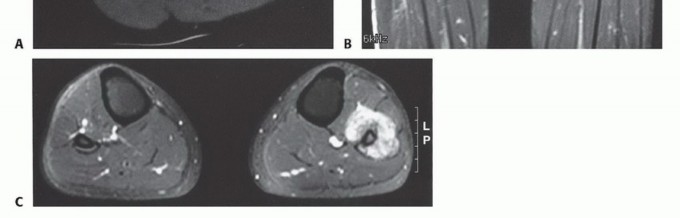

التصوير بالرنين المغناطيسي (MRI): يُعد MRI الأداة الأكثر قيمة لتقييم أورام العظام. يوفر صورًا مفصلة للأنسجة الرخوة المحيطة بالعظم (العضلات، الأوتار، الأعصاب، الأوعية الدموية)، ويحدد مدى انتشار الورم داخل العظم وإلى الأنسجة الرخوة المجاورة. وهو ضروري للتخطيط الجراحي للحفاظ على الطرف.

التصوير المقطعي المحوسب (CT Scan): يوفر صورًا تفصيلية لبنية العظم بدقة عالية، ويكشف عن تآكل القشرة العظمية، وتكوين العظم الجديد، وتكلسات الورم. كما يستخدم للكشف عن أي انتشار للورم إلى الرئتين (نقائل).